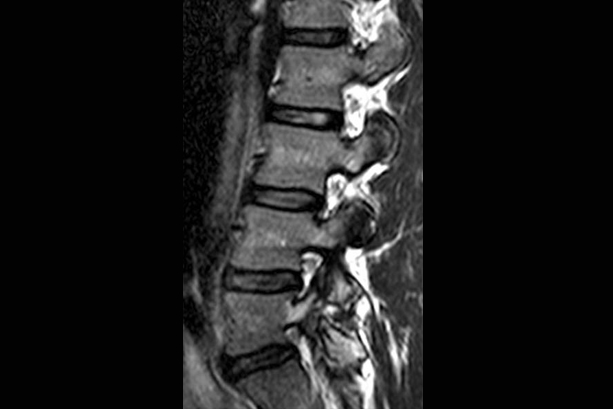

SRF TAKES PRIDE IN PRESENTING TO YOU A FEW INTERESTING CASES

More than 300 Underprivileged Patients have been Operated through our Foundation over the last 15 years !

book_4 Notable

Cases